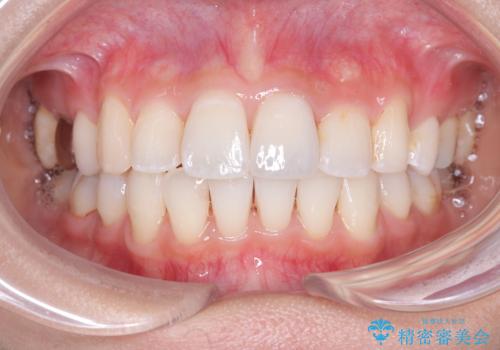

前歯のデコボコと深い咬み合わせを解消